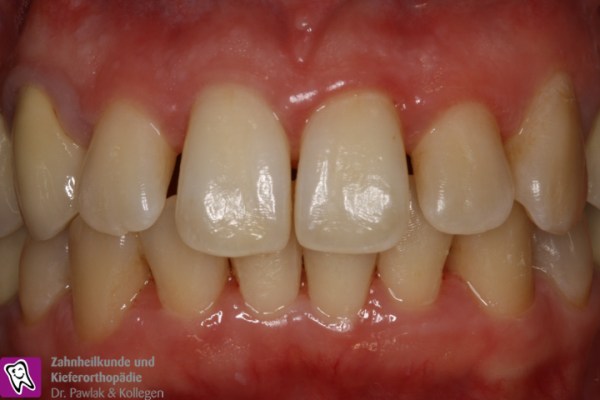

Frontzahnbereich vor Parodontitis-Behandlung mit entzündetem Zahnfleisch. Frontzahnbereich nach Parodontitis-Behandlung mit gesundem Zahnfleisch.